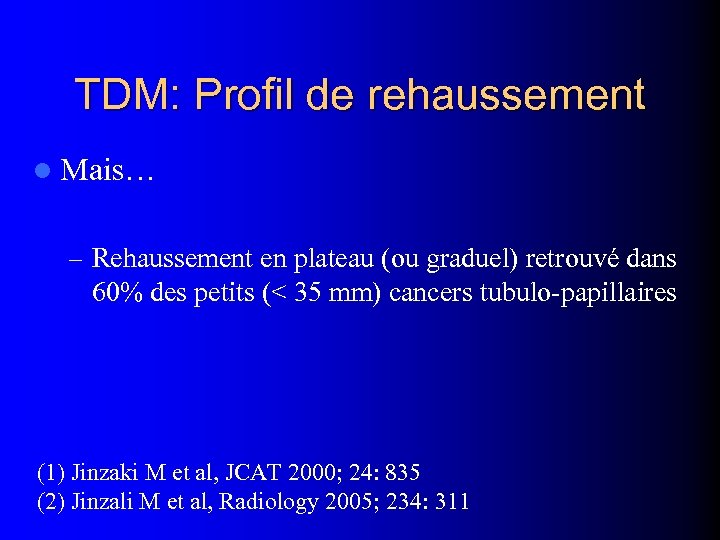

TDM: Profil de rehaussement l Mais… – Rehaussement en plateau (ou graduel) retrouvé dans 60% des petits (< 35 mm) cancers tubulo-papillaires (1) Jinzaki M et al, JCAT 2000; 24: 835 (2) Jinzali M et al, Radiology 2005; 234: 311

TDM: Profil de rehaussement l Mais… – Rehaussement en plateau (ou graduel) retrouvé dans 60% des petits (< 35 mm) cancers tubulo-papillaires (1) Jinzaki M et al, JCAT 2000; 24: 835 (2) Jinzali M et al, Radiology 2005; 234: 311